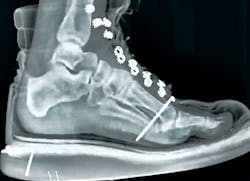

Caleb Miller had been a carpenter for about 18 months when he had a serious nail-gun accident. He was holding soffit framing in place with one hand, and pulling the contact trigger on his nail gun with the other.

Accidental firing from rebound or recoil is perhaps the most common way contact triggers cause injuries. “I thought I had my hand back far enough,” Miller says, “but … I shot my two fingers together.”

One finger came unstuck when he shook his hand, but the nail went clean through the other (photo opposite) and required a visit to the hospital to remove it.